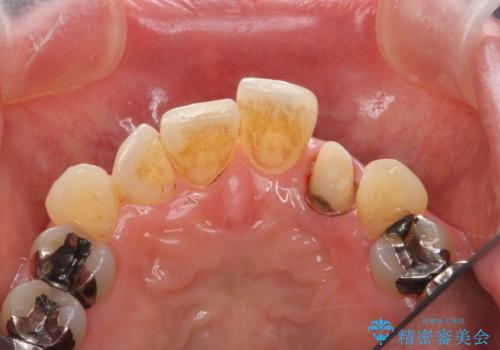

- 目立つ前歯の著しい変色の改善を求めて来院されました。

根管治療が為されたまま、クラウンの装着が行われず変色し審美障害を来している状態です。

維持を保つためのファイバーコア築盛を行い、精密なジルコニアクラウン製作を行います。